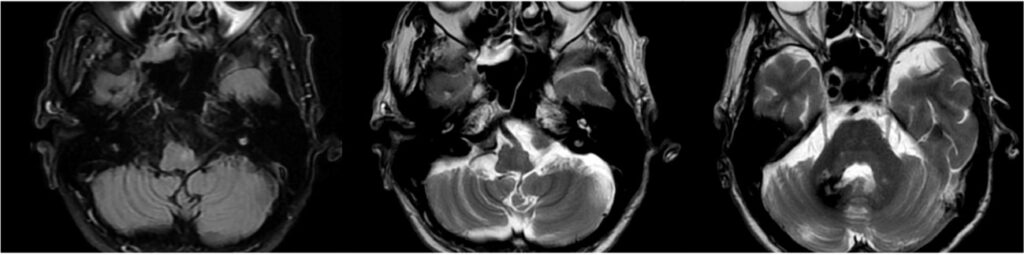

El compromiso estructural observado corresponde a una alteración del circuito dentato-rubro-olivar, cuyo daño es un mecanismo bien reconocido en la génesis de la degeneración olivar hipertrófica (DOH). En este contexto, la hiperintensidad de la oliva inferior en secuencias T2/FLAIR constituye el hallazgo imagenológico cardinal, permitiendo el diagnóstico incluso en ausencia de cambios volumétricos evidentes en fases iniciales.

La DOH representa una forma particular de degeneración transneuronal, secundaria a la interrupción de las conexiones aferentes de la oliva inferior, más frecuentemente asociada a lesiones estructurales del núcleo dentado, pedúnculo cerebeloso superior o núcleo rojo.(7) En las imágenes, este proceso se manifiesta inicialmente como un aumento de señal en T2 y FLAIR sin agrandamiento del núcleo, seguido, en fases intermedias, por incremento del volumen olivar y, finalmente, por una etapa tardía de normalización volumétrica o atrofia, con persistencia de la hiperintensidad.(8)

La identificación de estos cambios evolutivos dependientes del tiempo resulta fundamental para una correcta interpretación de las imágenes, ya que la DOH puede simular otras entidades infiltrativas o neoplásicas del tronco encefálico si no se reconoce su patrón característico.(9) En este caso, la coexistencia de una lesión estructural hemorrágica crónica en el pedúnculo cerebeloso derecho refuerza la relación causal con el compromiso contralateral de la oliva inferior.

Desde el punto de vista clínico, esta alteración anatómica se asocia clásicamente con temblor palatino sintomático, ataxia cerebelosa y alteraciones de la coordinación, aunque la expresión clínica puede ser variable y no siempre proporcional a los hallazgos en la neuroimagen.(7-9)